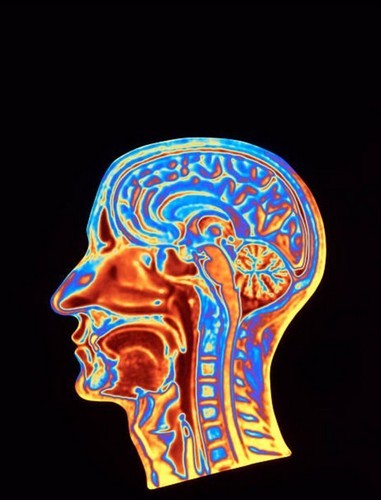

טיפול נוירופידבק, הידוע גם בשם ביופידבק א.א. ג. (EEG), הוא טכניקה לא פולשנית המשתמשת במשוב בזמן אמת כדי לעזור לאנשים ללמוד לשלוט בפעילות המוח שלהם. טיפול נוירופידבק הוכח כיעיל בטיפול במגוון רחב של מצבים, כולל קשיי שינה כגון אינסומניה.נויררופידבק רחובות-טיפול בקשיי שינה

NF (נוירופידבק) היא תת-קטגוריה של ביופידבק, טכניקה שבה לומדים לווסת תפקודים גופניים, כמו דופק, באמצעות משוב. לשם כך, ביופידבק משתמש בגירויים שונים התואמים את המאפיינים הפיזיולוגיים של האדם ומציג אותם ללקוח (משוב). לאחר מכן, הלקוח משתמש במידע זה כדי לשנות את התפקוד הפיזיולוגי שלו. במקרה של NF, האותות הפיזיולוגיים המשמשים ומווסתים הם גלי מוח.